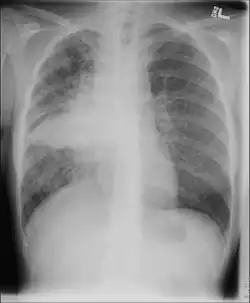

| Image demonstrates widespread pulmonary disease with associated lymphadenopathy consistent with pulmonary coccidoidomycosis | |

Primary pulmonary coccidioidomycosis is an infection caused by inhalation of Coccidioides immitis.[1]: 314 Once pulmonary symptoms subside, about 30% of women and 15% of men will have allergic skin manifestations in the form of erythema nodosum.[1]: 314 A coccidioidoma is a benign localized residual granulomatous lesion or scar that can remain in the lung's tissues following primary pulmonary coccidioidomycosis.[2]